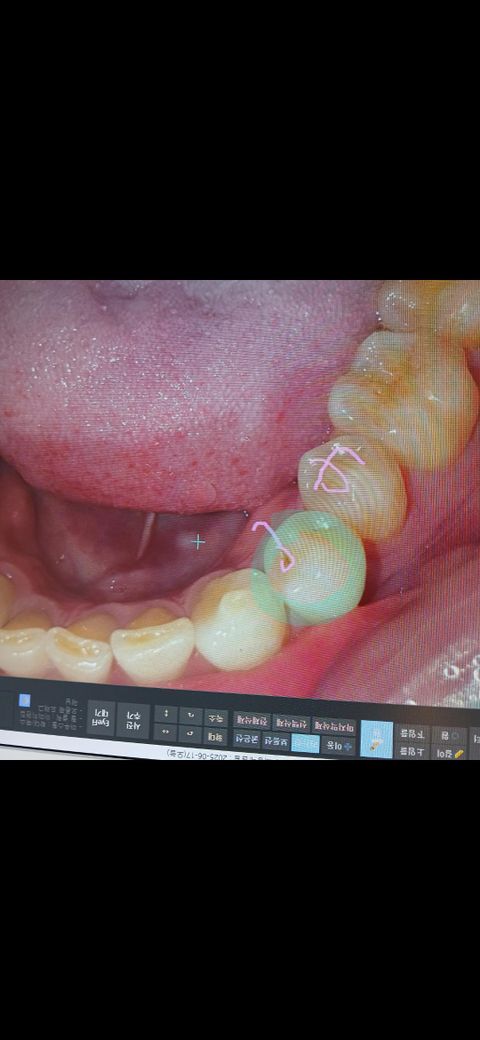

예를들어 아래사진에 해당되는 치아는

바로 레진을 하자고 하는데

적절한 조치인지 여쭤봅니다

(폰으로 찍은사진)

(치과에서 찍은사진)

• 1번 째 사진

• 2번 째 사진